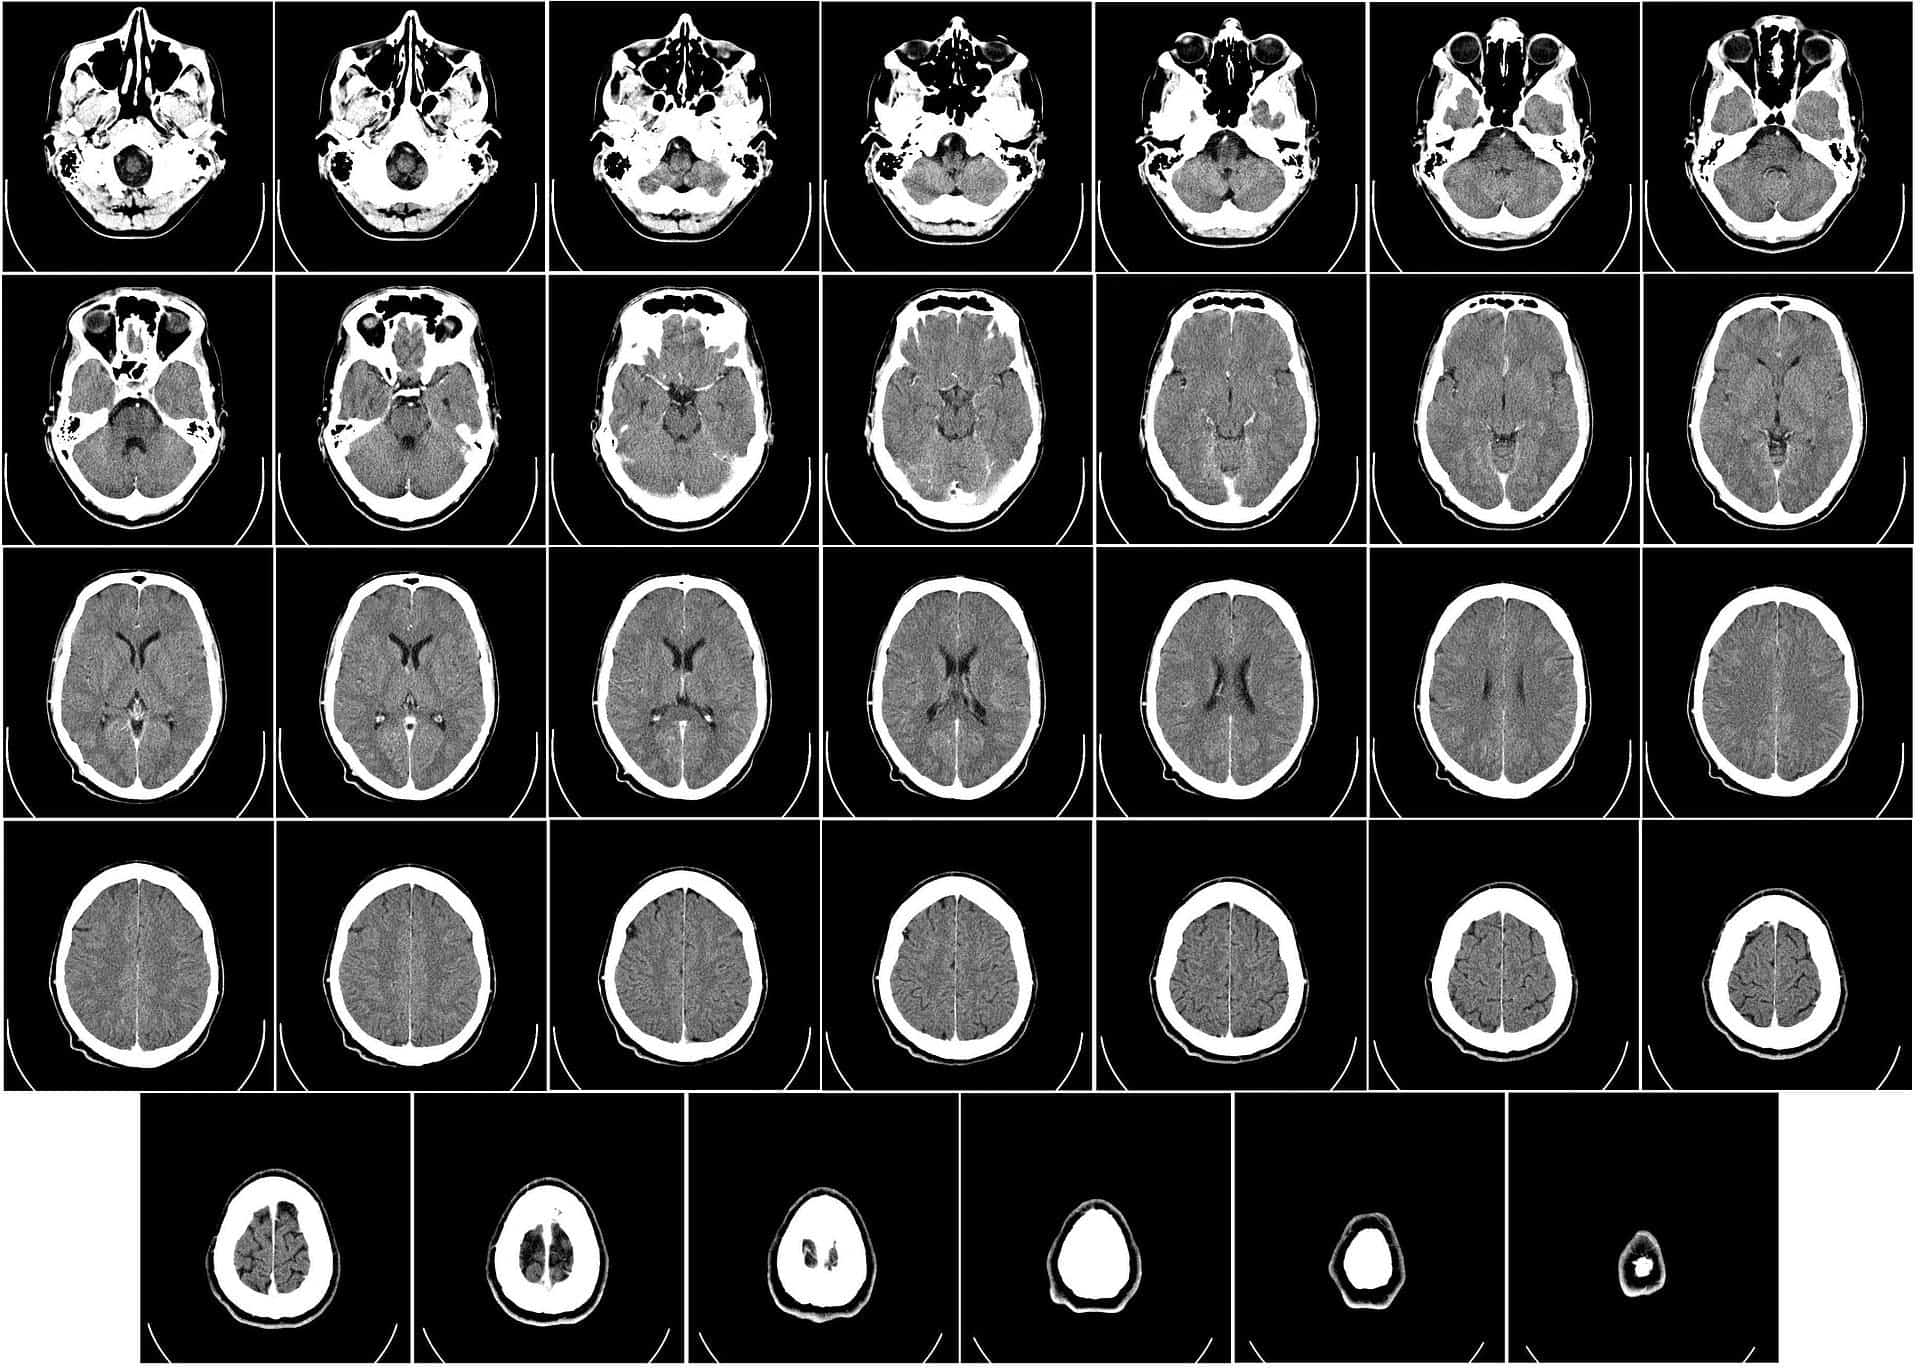

White matter vs. gray matter Black And White Matter Meaning Oftentimes, journaling about your thoughts can help you see them in a different light, improving your ability to look at them more. Things are either all bad or all good. Learn how gray and white matter in the central nervous system differ in their location and function, as well as how various diseases affect. Black and white thinking is the. Black And White Matter Meaning.

White matter and Grey matter crosssection Brain scan, Mri scan, Mri Black And White Matter Meaning The use of the words white and black to describe people’s skin (and yellow and red, which are offensive, and brown, which is often. Black and white thinking is the tendency to see things in extremes. If something is in black and white, it means one has to be correct and second has to be incorrect; Learn more about what. Black And White Matter Meaning.

Anatomyphysiology162 Figure 12 Gray Matter and White Matter A brain Black And White Matter Meaning Learn more about what it is, what causes it, and what you can do. Black and white thinking is when someone thinks in extremes. Oftentimes, journaling about your thoughts can help you see them in a different light, improving your ability to look at them more. Learn how gray and white matter in the central nervous system differ in their. Black And White Matter Meaning.

Gray Matter vs White Matter Difference and Comparison Black And White Matter Meaning Oftentimes, journaling about your thoughts can help you see them in a different light, improving your ability to look at them more. If something is in black and white, it means one has to be correct and second has to be incorrect; Black and white thinking is the tendency to see things in extremes. Learn more about what it is,. Black And White Matter Meaning.

Gray vs. White Matter Location, Differences & Function Lesson Black And White Matter Meaning Learn how gray and white matter in the central nervous system differ in their location and function, as well as how various diseases affect. Black and white thinking is the tendency to see things in extremes. Learn more about what it is, what causes it, and what you can do. Things are either all bad or all good. If something. Black And White Matter Meaning.